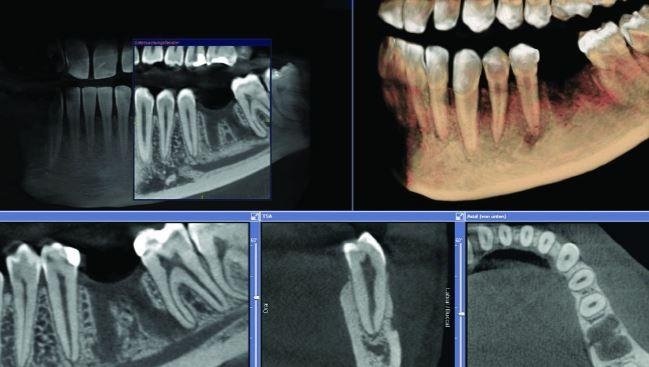

•  DENTAL IMPLANTS